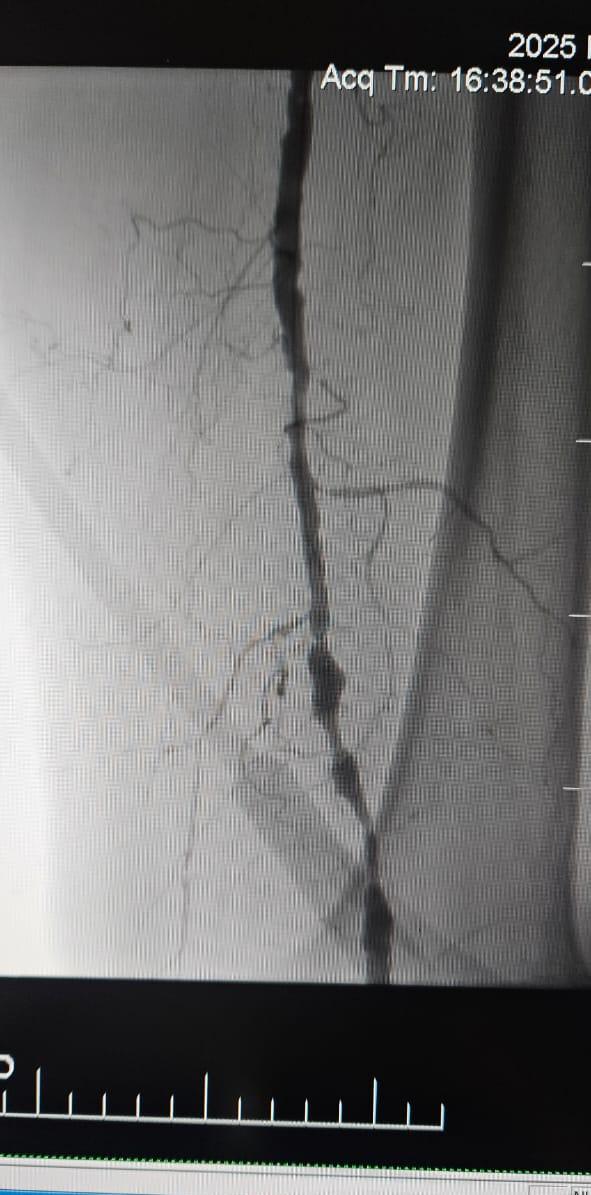

Temos o prazer de compartilhar um caso de sucesso de um hospital em Batumi, Geórgia, onde uma paciente de 78 anos com Isquemia Crítica do Membro (CLI) causada por oclusão total crônica da artéria do membro inferior apresentou notável melhora clínica após o tratamento com o Sistema de Dilatação de Balões Periféricos ThorCrack IVL.

Este caso ressalta o valor clínico da litotripsia intravascular (IVL) no tratamento de casos complexos de CLI com oclusão crônica de segmento longo-particularmente em pacientes com calcificação pesada, onde balões tradicionais ou dispositivos de aterectomia podem ter eficácia limitada.